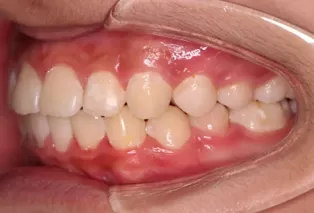

Photos intra-orales